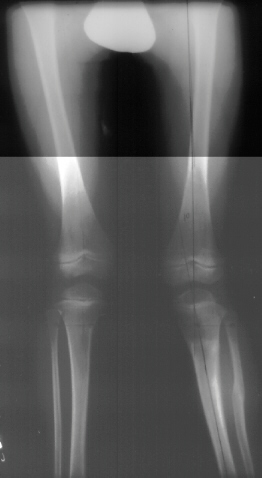

X-Ray Set 4. 3 Months post Surgery , Left 6* Mechanical axis

X-Ray Set 5. 9 Months post Surgery Left 10* Mechanical axis